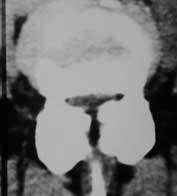

Lendenwirbelsäule

Auch hier reicht zumeist Röntgenaufnahme in Funktion sowie eine Kernspintomographie oder eine Computertomographie aus. Bei einem Wirbelgleiten oder einer Verengung auf mehreren Höhen ist eine Myelographie nach wie vor die Untersuchung, die die wertvollsten Ergebnisse im Hinblick auf eine genaue Operationsplanung liefert.